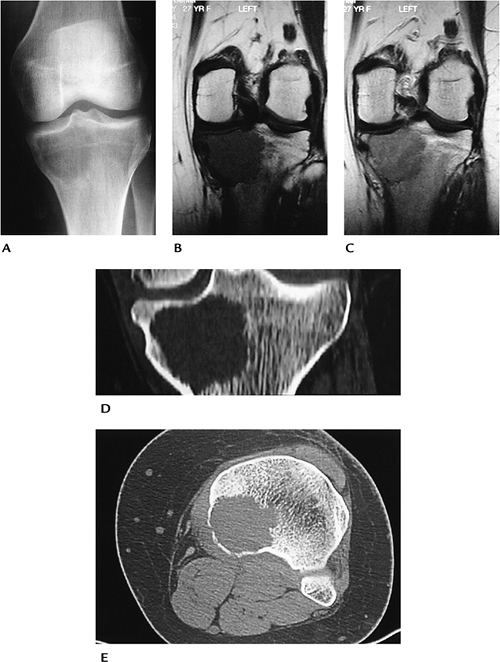

Bone Tumors/Tumorlike Conditions: Giant Cell Tumor

Giant cell tumors account for 22.7% of

benign bone tumors. Patients present with pain and swelling in the

involved site. A tender palpable mass commonly present.

-

Age: 20 to 40 years

Sex: Females affected slightly more frequently than males.

Common locations: most involve the distal

femur or proximal tibia (46%) followed by the distal radius and sacrum.

Epiphyseal location. -

Imaging features:

Radiographic features: lytic lesion with

nonsclerotic margins originating in the metaphysis but extending to

subchondral bone. Cortical breakthrough in 33% to 50% of cases. -

CT: similar to radiographs. No tumor matrix.

MRI: low intensity on T1-weighted and

intermediate signal on T2-weighted sequences. T2 sequences may show

decreased signal because of hemosiderin deposition. In some cases,

signal intensity increased on T2-weighted images. May have fluid–fluid

levels. Enhanced on post-contrast images.

Differential diagnosis:

Chondroblastoma

Osteosarcoma

Fibrosarcoma

Malignant fibrous histiocytoma

Treatment: resection with grafting or, in some cases, joint prosthesis

P.670

![]() |

|

FIGURE 10-22 Giant cell tumor. (A) AP radiograph demonstrates a poorly defined lesion involving the epiphysis and metaphysis. Coronal T1- (B) and postcontrast T1-weighted (C) images show low signal intensity on the T1-weighted image (B) and contrast enhancement (C). Coronal (D) and axial (E) CT images showing low attenuation with no calcified matrix.